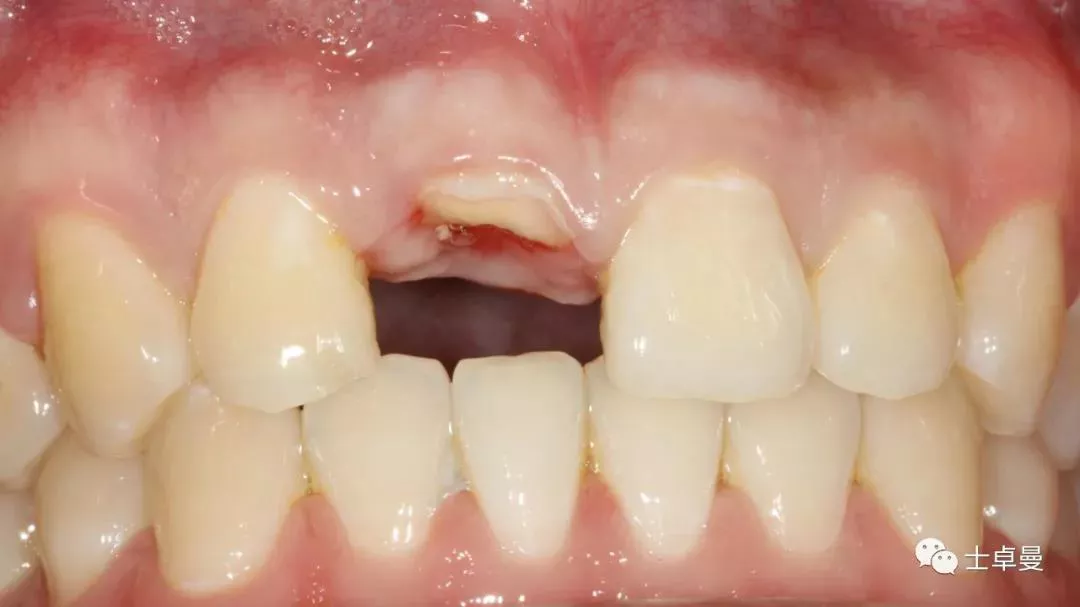

分根

拔出腭侧牙根

保留唇侧牙片

牙周探针探查牙片位置及松动度